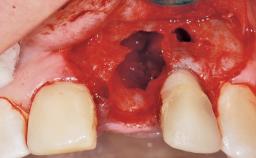

Immediate Flapless Placement of an Implant in a Maxillary Right Lateral Incisor Site

This 43-year-old male patient, a non-smoker, came to our practice because of a fracture of tooth 12 caused by a bicycle accident. Due to the combined para- and infrabony crown and root fracture, tooth extraction, and subsequent implant placement were suggested to the patient as the therapy of choice. The patient had high esthetic expectations with regard to the treatment outcome and asked for an immediate fixed provisional restoration. His individual esthetic risk profile summed up to a medium esthetic risk.

Soft Tissue Anatomy Intact Defective

Bone Volume Horizontally and vertically sufficient Horizontally deficient Deficient vertically or deficient vertically AND horizontally

Soft Tissue Contour and Volume Ideal